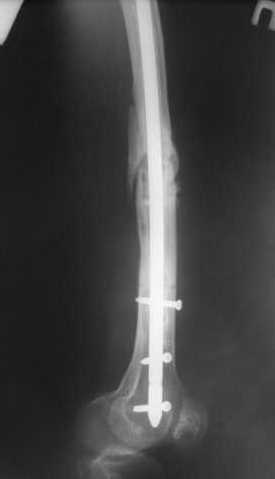

В приложении как раз видна эволюция использововшихся у нас большеберцовых гвоздей. Первый - дизайн как у UTN, второй - разнесены 45 градусные отверстия (зачем их вообще изначально так нелепо на одном уровне сделалм???), третий - убрано сиавшее лишним статическое отверстие, Herzog's bend перемещен более проксимально.